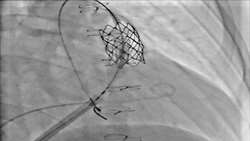

تاویحکیم تهیه کننده: مریم سادات مشعشعی تصاویر مطالب مرتبط شروع موفقیت امیز اینترونشن در کودکان مبتلا به بیماریهای قلبی ساختاری مادرزادی در بخش انژیوگرافی بیمارستان فوق تخصصی کودکان حکیم بیمارستان...